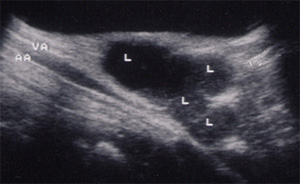

Gli esami ematologici dimostrano: VES= 28 ,modesta leucocitosi neutrofila,, transaminasi normali, sierologia per EBV Toxo e citomegalovirus negativa , Mantoux negativa. Anticorpi antiBartonella IgG < 1:128. L'ecografia delle parti molli ascellari a destra descrive un pacchetto linfonodale composto da 5-6-linfonodi, di cui uno di dimensioni 20x30 mm, colliquato comprimente la vena ascellare.

Una particolare forma sistemica di malattia da graffio di gatto è quella denominata granulomatosi epato-splenica multifocale caratterizzata da presenza di lesioni focali ipoecogene con diametro compreso tra 8 e 20 mm. a livello epatico e/o splenico,con normalità dei parametri di citolisi epatica. Queste lesioni evolvono verso la guarigione con totale scomparsa o con calcificazioni residue nel giro di 5-6 mesi.